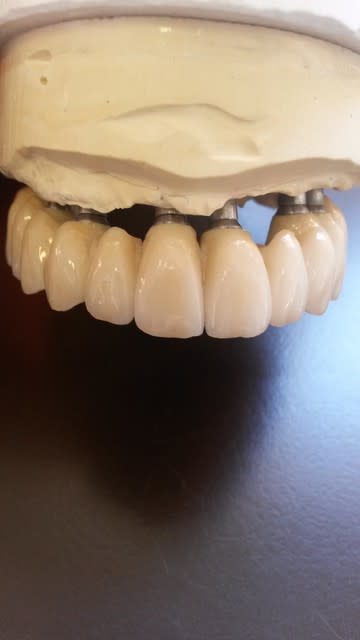

bonjour, pour des implantos exclusifs c'est surement fréquent, mais pour un omnipraticien comme moi, c'est pas tout les jours ! j'étais content en fin de traitement.

joli, 10 implants intelligemment répartis, même si un de perdu.